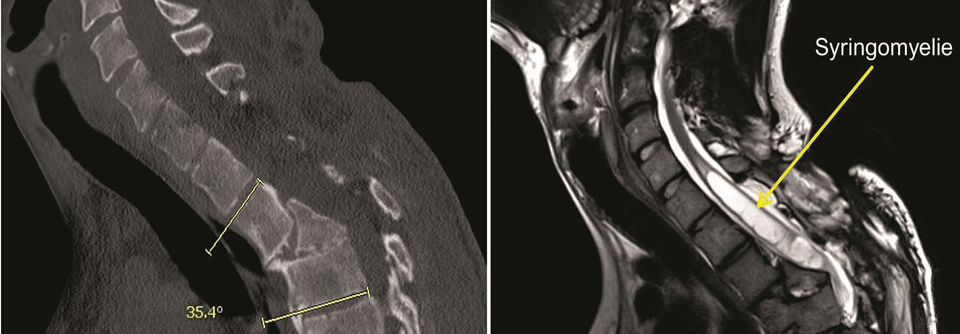

Prof. Courtine hat das Verfahren zusammen mit der Neurochirurgin Professor Dr. Jocelyne Bloch vom Universitätskrankenhaus Lausanne deutlich weiterentwickelt. Dank seiner STIMO-Technik (Stimulation Movement Overground) gelang es drei Männern nach einer jahrelang zurückliegenden traumatischen Halswirbelsäulenverletzung und unvollständiger Querschnittlähmung erstmals, auch nach Abschalten der elektrischen Impulse zu gehen. Wurde das unter die Haut implantierte Gerät angelassen, konnten sie sich freihändig und teilweise ohne Körpergewicht-Entlastung durch Stütze oder Aufhängung selbstständig über längere Strecken fortbewegen.